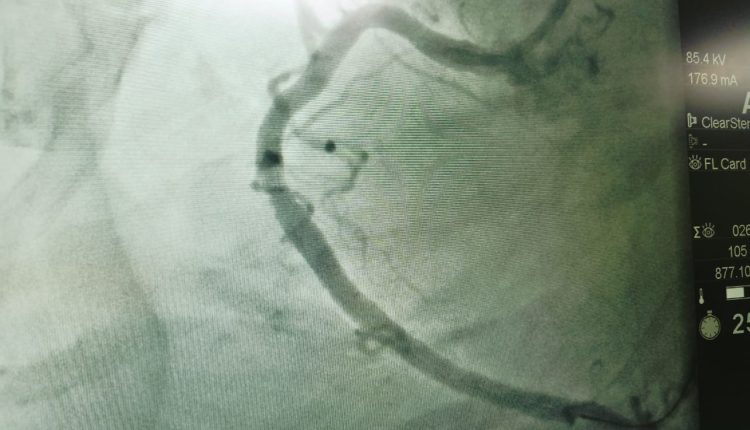

وأشار محمود عبدالفتاح مدير الإعلام والعلاقات العامة بالمديرية، إلى أن حالات القسطرة القلبية المائة التي تم إجراؤها بمستشفى فاقوس المركزي منذ تشغيل الوحدة في ٢٤ فبراير الماضي، تنوعت ما بين ٥٩ حالة قسطرة تشخيصية، و٤١ حالة قسطرة علاجية والتي تضمنت تركيب دعامات وتوسيع الشرايين باستخدام البالون، وتم خلالها إنقاذ حياة العديد من الحالات الطارئة الحرجة، وتم خروج جميع المرضى بفضل الله بحالة جيدة، بعد تقديم الرعاية الطبية اللازمة لهم قبل وبعد إجراء القسطرة القلبية بالمستشفى.